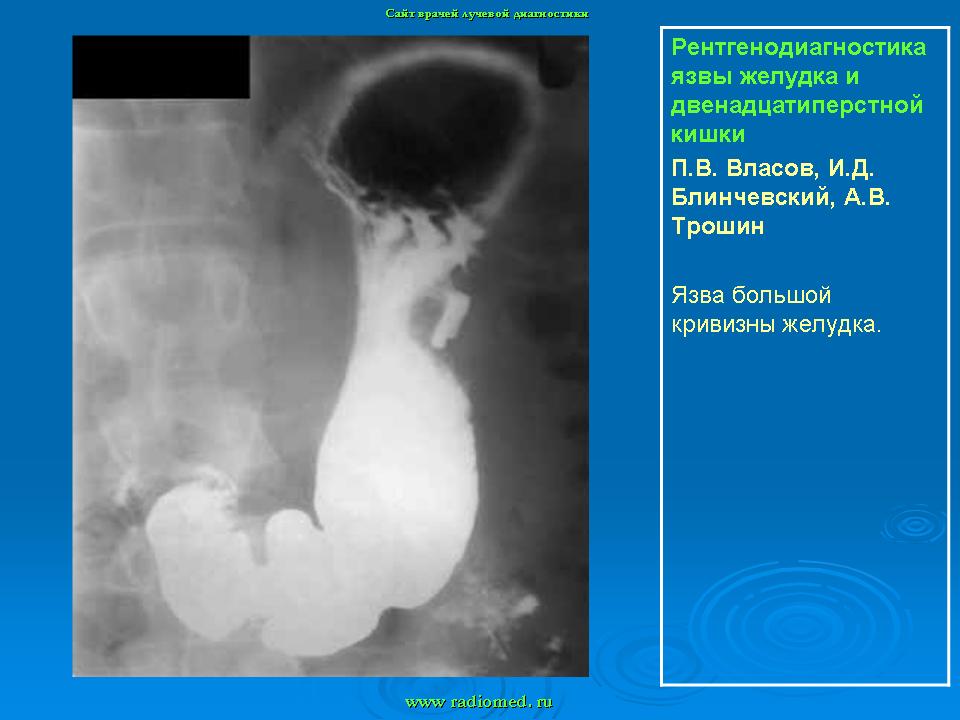

Пищеварительная система. Рентгенодиагностика язвы желудка и 12-ти перстной кишки. +

Рентгенодиагностика язвы желудка и 12-ти перстной кишки.